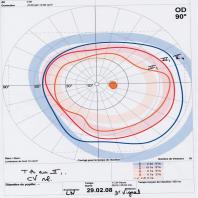

- eFig. 10-13 - Niveau de sévérité pressionnelle d?un GPAO à partir de courbes diurnes de PIO